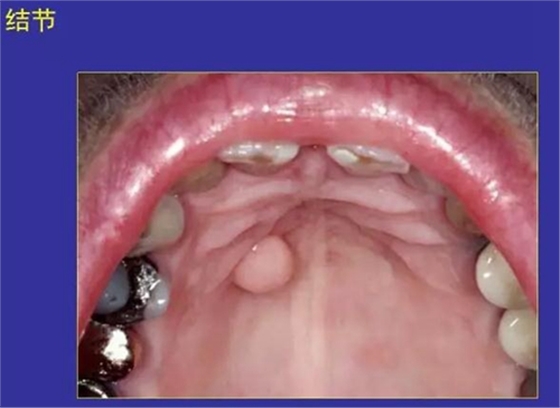

11.結(jié)節(jié):突起或突起于口腔黏膜的實體病損。

纖維瘤、痣

正??谇火つぜ俺R姴p圖